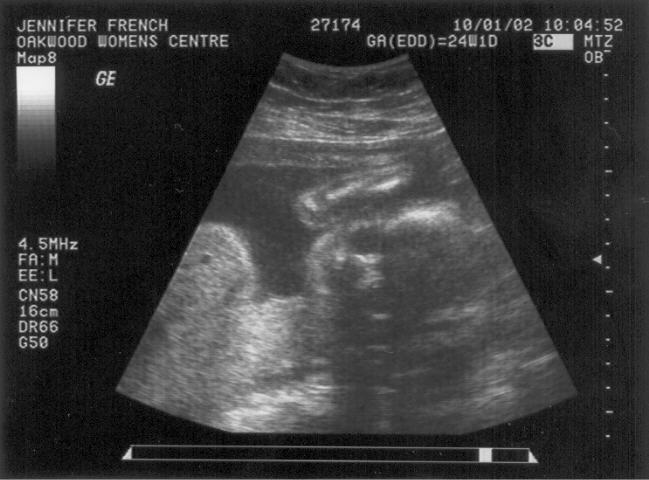

It’s a Girl Posted on October 29, 2002 by Jason We went to the doctor today and found out that Abby is going to have a little sister. We are very excited to be having another girl. I’m sure Abby is thrilled as well. The big debate on names has begun. Share this: Share on X (Opens in new window) X Share on Facebook (Opens in new window) Facebook Like Loading... Related